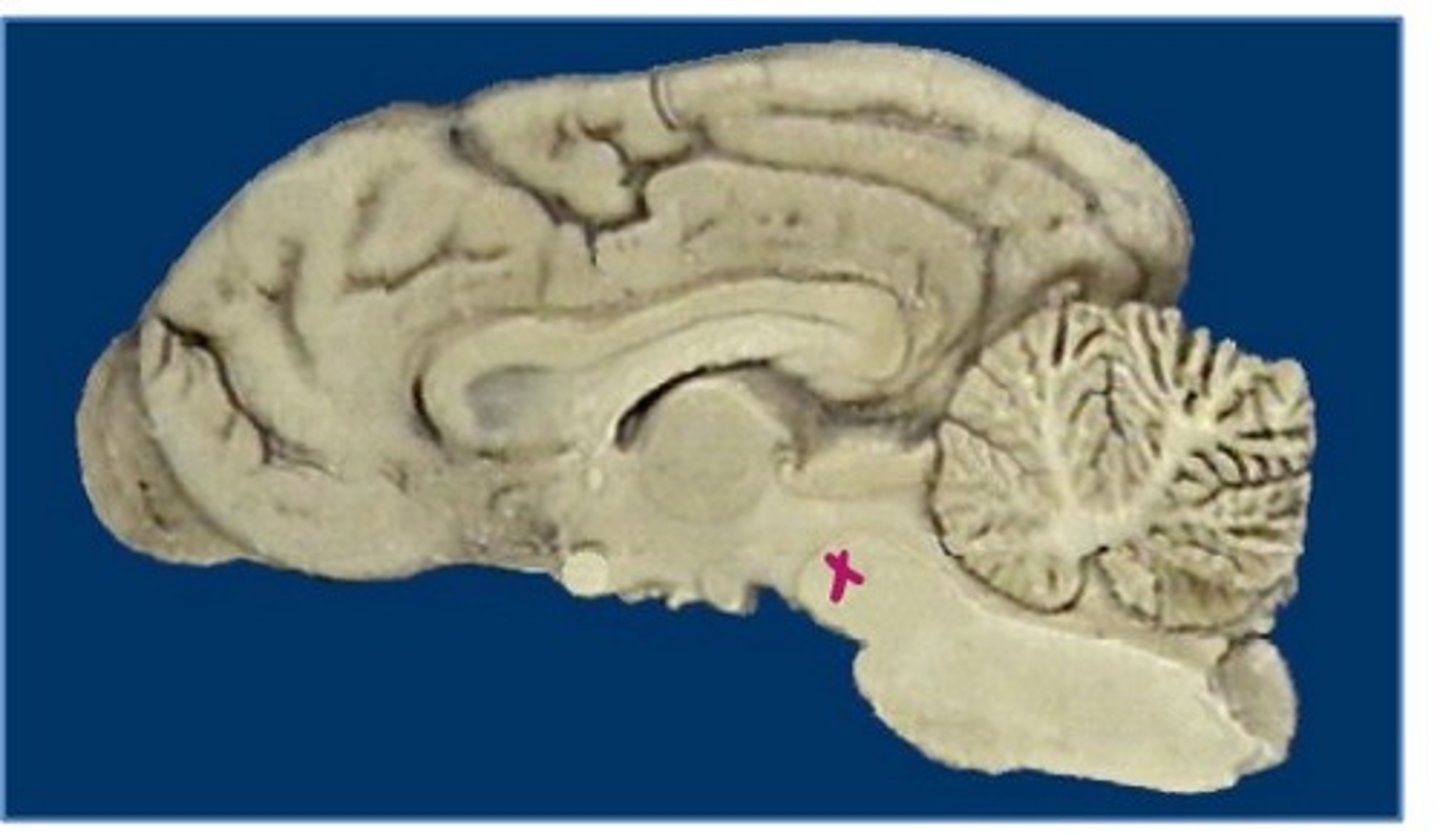

what forms the outermost layer of the brain?

gray matter

what makes up the sulci and gyri?

what forms the central aspect of the brain?

white matter

what forms the peripheral aspect of the spinal cord (ascending and descending pathways)?